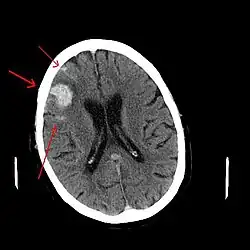

Los hematomas epidurales son los que se localizan entre la lámina interna craneal y la duramadre. Como se ha mencionado están asociados con fracturas de cráneo y ruptura de la arteria meníngea media o sus ramas. Son más comunes en las regiones parietales y temporales y son raros en las regiones frontales y occipitales. Se encuentran entre el 8% y 10% en pacientes con TCE grave. En la TAC, se ven como lesiones hiperdensas y biconvexas y debido a que no existe un espacio entre la duramadre y el hueso no suelen propagarse a menos que superen la adherencia de la duramadre. Estos hematomas son raros en infantes debido a que el cráneo es deformable lo que les confiere una protección. Además son raros en adultos mayores de 60 años debido a la adherencia débil de la duramadre al cráneo.[15]

Los hematomas subdurales se encuentran entre la cara interna de la duramadre y la superficie cerebral. Se encuentra entre el 20% y el 25% en pacientes con TCE grave. Son el resultado de hemorragia en las venas anastomóticas de la corteza cerebral superficial o ruptura de los senos venosos o sus tributarios y se asocian con daño en el tejido cerebral subyacente. Más específicamente se ha demostrado que un buen número de estos hematomas se deben a la ruptura de venas puente parasagitales.[31][32] Normalmente se expanden en la mayor parte de la convexidad cerebral pero no pueden propagarse al hemisferio contrario debido a la existencia de la hoz del cerebro. Los hematomas subdurales se clasifican en agudos, subagudos o crónicos dependiendo de la aparición y duración de estos y su aspecto característico en la TC:[15]

- Hematomas subdurales agudos: se observan hasta los 3 días de la lesión y en una TC su aspecto es de manchas con color blanco brillante.

- Hematomas subdurales subagudos: se observan desde los 3 días hasta las 3 semanas del trauma y su aspecto en TC es isodenso con relación al tejido cerebral, usualmente se confunden y son pasados por alto.

- Hematomas subdurales crónicos: se producen desde las 3 semanas hasta los 3 meses después del trauma y su aspecto en TC es hipodenso con relación al tejido cerebral.

Las contusiones se encuentran en 20% al 25% de los pacientes con TCE grave. Son lesiones heterogéneas compuestas de zonas de hemorragia puntiforme, edema y necrosis que aparecen en las imágenes de TC como áreas de hiperdensidad puntiforme (hemorragias), con hipodensidad circundante (edema), suelen estar localizadas en la cara inferior del lóbulo frontal y la cara anterior del lóbulo temporal por su relación con el ala mayor del esfenoides. También se pueden encontrar en la superficie de impacto y en la superficie contraria a este, el llamado efecto golpe-contragolpe. Cuando estas evolucionan se parecen más a los hematomas intracerebrales y su ubicación depende el posible efecto de masa.